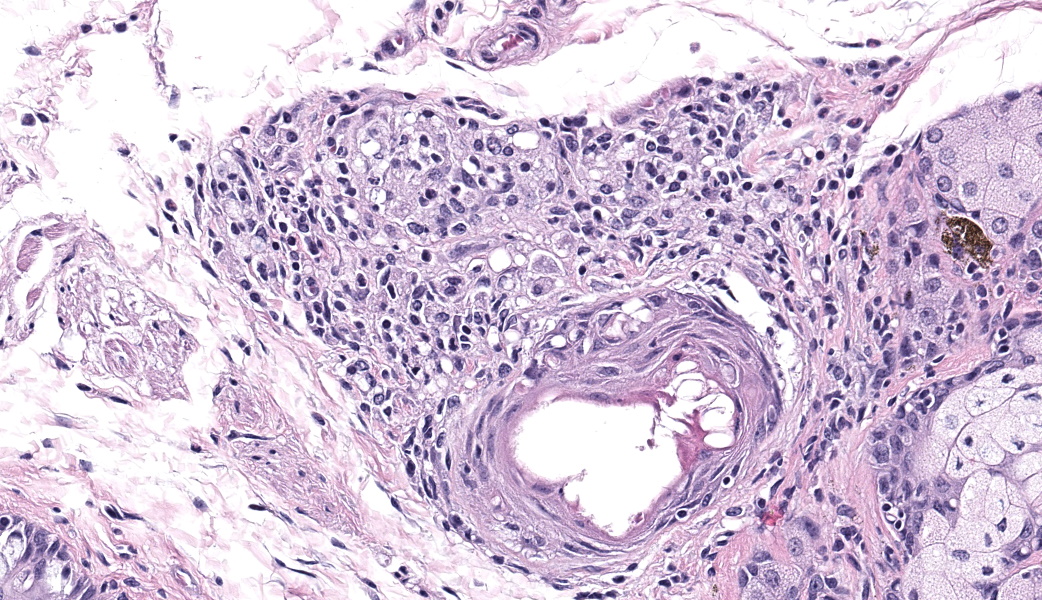

Bilaterally or unilaterally*, the eyelids contained locally extensive epidermal acanthosis and ortho to parakeratotic hyperkeratosis of varying severity. This was accompanied by epithelial erosion and mild serocellular crusting. There was mild to moderate mixed neutrophilic to lymphocytic inflammation within the conjunctiva and eyelid sebaceous glands (Meibomian glands). Focally there was occasional dilation and mild degeneration of Meibomian gland acini or ductules. The cornea, lens, iris, retina, optic nerve and other interior structures of the eyes were normal.

- Eyelids: Blepharoconjunctivitis, neutrophilic, with epidermal acanthosis, erosions, and ortho to parakeratotic hyperkeratosis, unilateral to bilateral, moderate, chronic.

- Eyelid: Blepharoconjunctivitis, unilateral, lymphocytic and neutrophilic, chronic, diffuse, mild, with epidermal hyperplasia and erosion.

- Eyelid, Meibomian gland: Adenitis, lymphoplasmacytic, chronic, focal, mild.